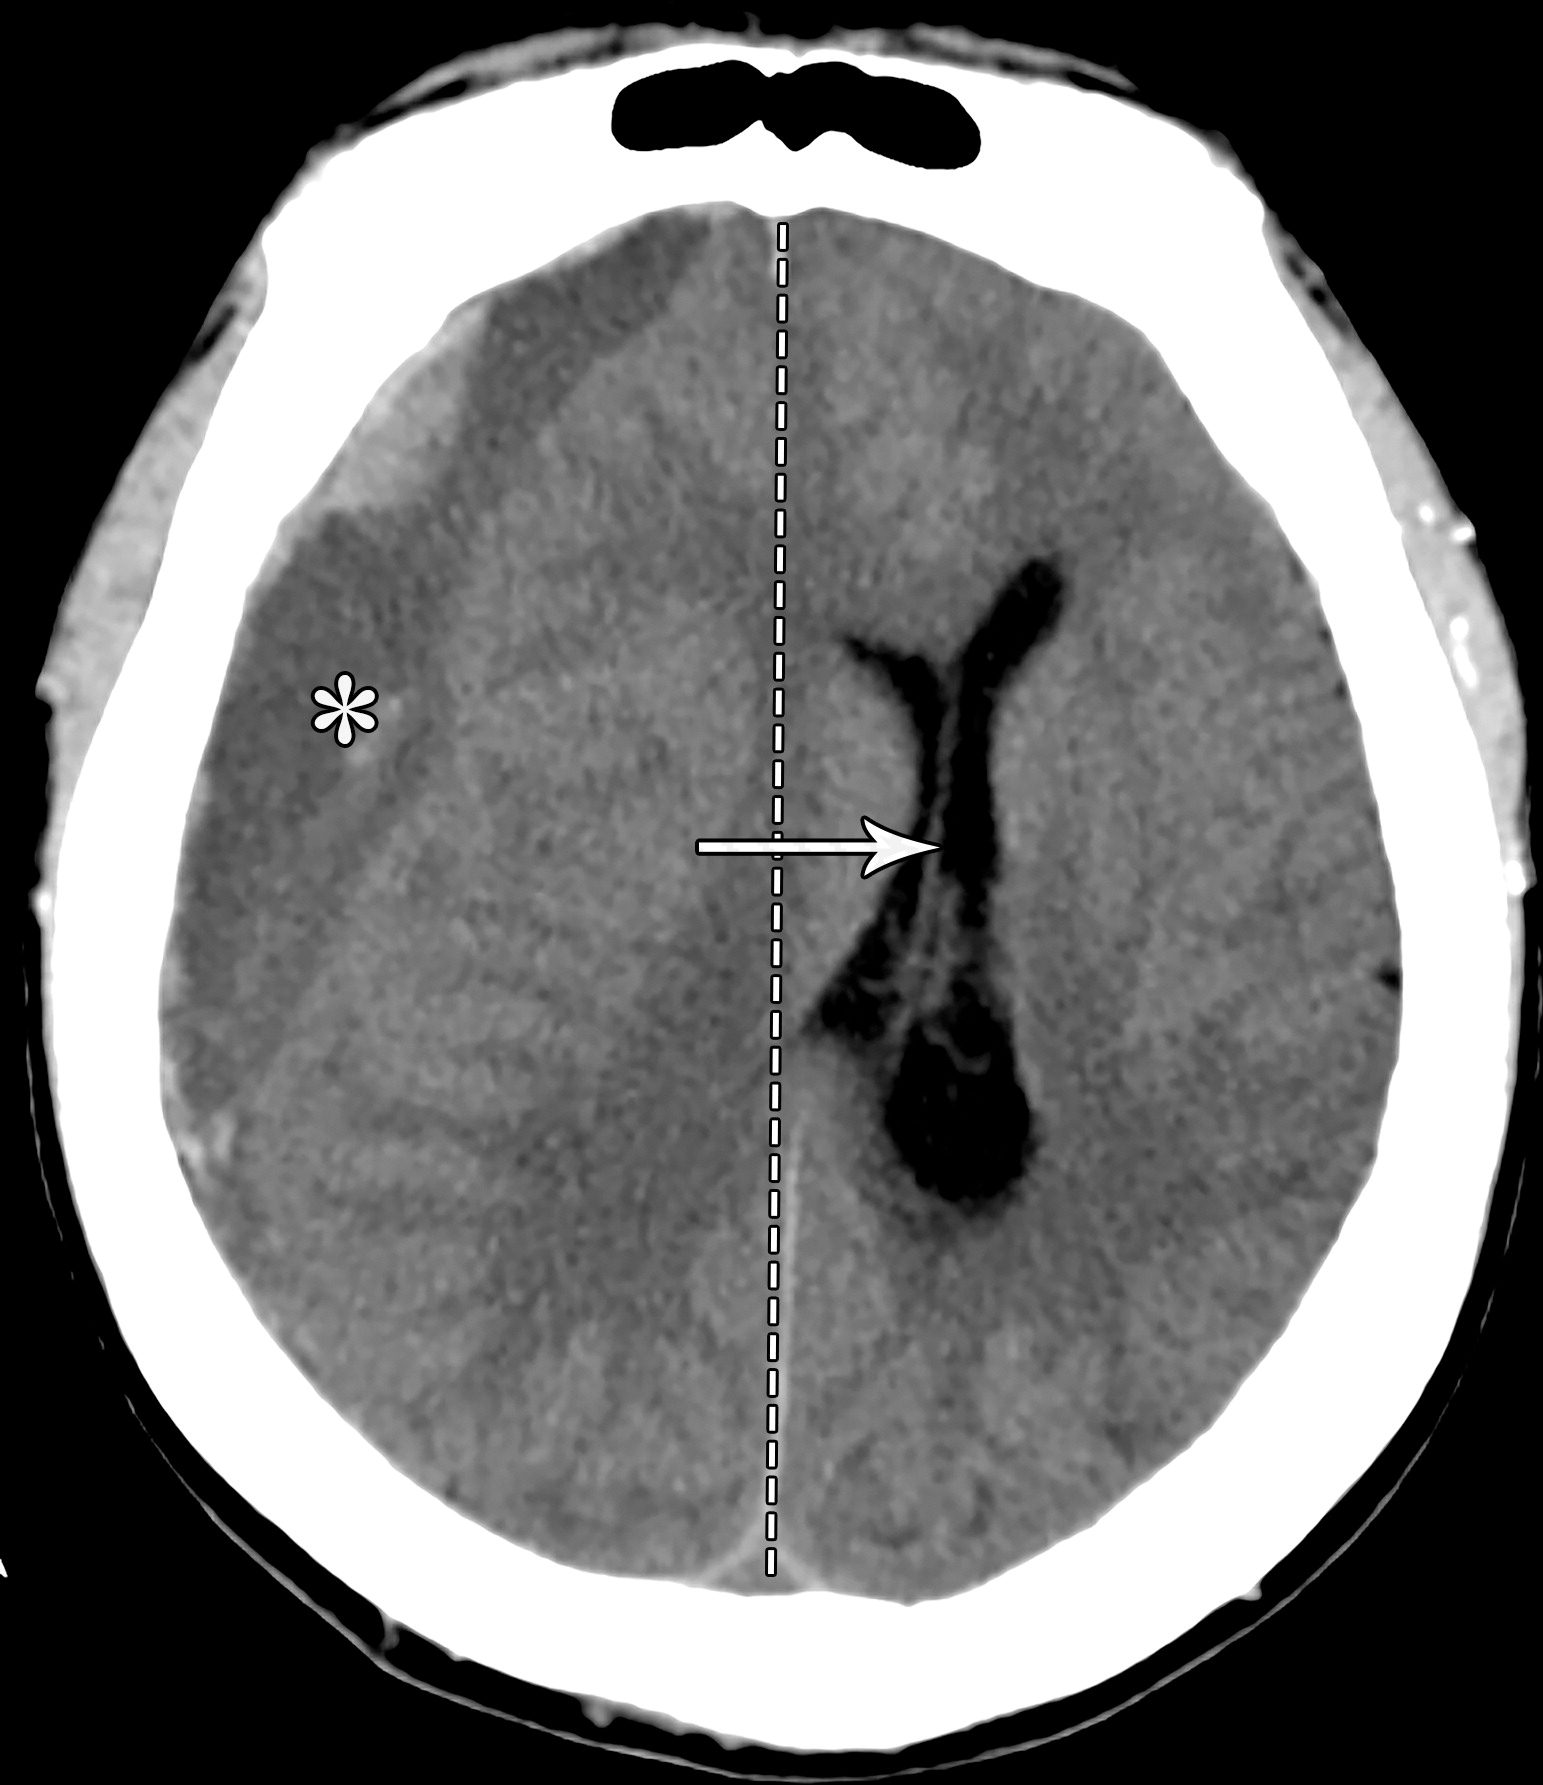

大脑镰下疝。平扫轴位CT示:右侧硬膜下血肿(*)伴混合密度影,表明处于不同时期的血液,血肿推挤使透明隔相对于中线(白色虚线)向左侧移位(白色长箭头)。右侧侧脑室受压,但是左侧侧脑室扩张。

33岁男性,生殖细胞肿瘤脑转移患者的大脑镰下疝:冠状增强CT示大脑穹隆游离缘下方的扣带回从左向右疝入(白色弯箭头),并伴同侧胼胝体(*)的下侧移位,注意同侧脑室受压和对侧脑室的扩张(白色箭头)。